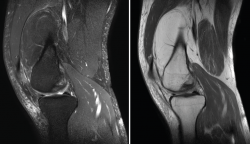

Figura 43. Corte sagital oblicuo T2 de resonancia magnética de rodilla: plastia del ligamento cruzado anterior íntegra.

Figura 44. Corte de secuencia sagital T2 Fat-Sat y T2 de resonancia magnética de rodilla: rotura de plastia del LCA.